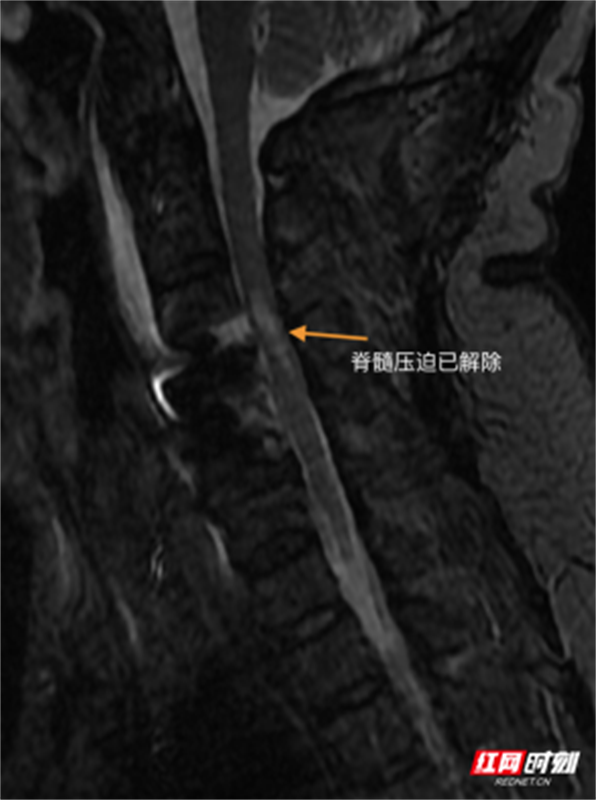

面对紧急的病情,副院长、脊柱外科主任李世芳带领团队迅速评估,决定采用目前脊柱内镜微创技术——Endo-ACDF(内镜下前路颈椎间盘切除融合术),实施了C3/4、C4/5节段的内镜下减压融合手术。该技术通过天然颈前间隙建立微小通道,在水介质下通过内镜放大视野,能够精准地切除压迫脊髓的突出椎间盘,并植入椎间融合器稳定颈椎。其优势在于创伤极小,出血极少,能最大程度保护周围正常组织结构。

术后患者恢复迅速。术后第三日,在医护人员指导下已可实现生活自理,肢体肌力与感觉功能显著改善。此次从完全受限到重获活动能力的成功救治,这场与时间赛跑的急救,体现了团队对脊柱急危重症的快速诊断能力、应急决策水平与现代微创技术的有效应用,为保障区域民众脊柱健康提供了可靠技术支持。